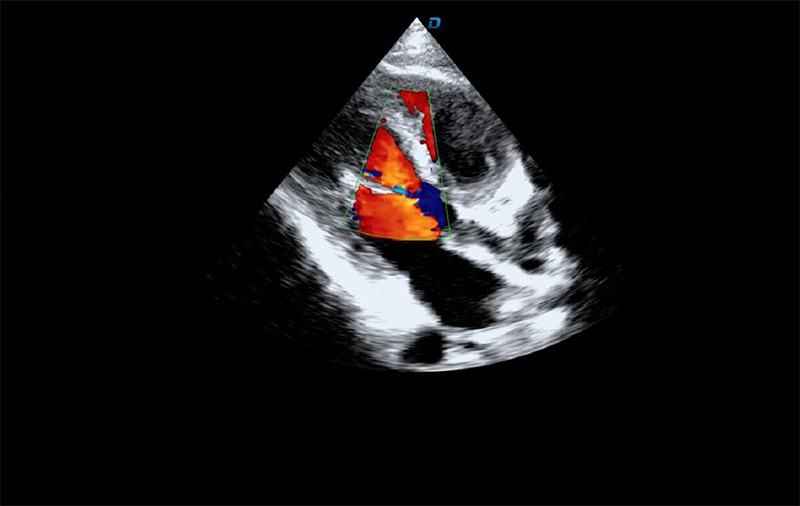

心脏彩超机检查

有些心脏病会引起心脏电活动的改变,但是有些心脏的疾病却不影响心电,而只影响心脏本身的结构。比如心脏扩大,心脏收缩无力,心脏的瓣膜关闭不严密,这些疾病的诊断及发现更多的依赖于心脏彩超,这些病变一般不随症状的缓解而缓解。心脏超声心动图,不需要开胸,就可以看到心脏的大小、内部结构、瓣膜运动情况等。除了探头压迫可能会有疼痛或不适感外,对患者没有任何创伤。

临床上,心脏超声心动图主要用于对各种先心病、心脏瓣膜病的诊断;各种心肌病、心包疾病的诊断和心脏功能的评估。部分严重肺气肿、胸廓畸形等患者,因为超声图像质量欠佳而诊断效果受到一定限制。